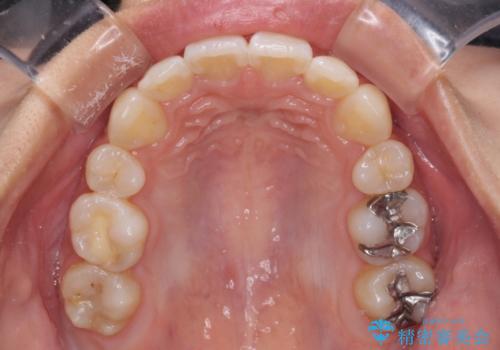

半年ほどで前歯のデコボコは改善され、汚れの溜まりやすさは解消されました。

抜歯スペースを閉じるために期間がかかりましたが、当初予定通り2年強で終えることができました。